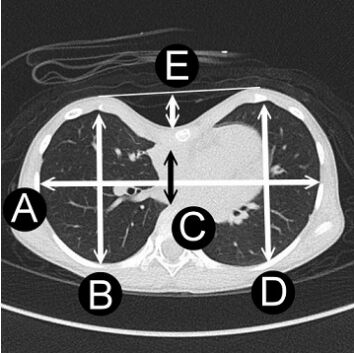

48.Haller index或稱凹陷指數,常用於漏斗胸(pectus excavatum)的嚴重度評估,是由Dr. Haller等人在 1987年所提出來的方法,圖中A為白色橫向雙箭頭線長度;B、D分別為左右兩側白色縱向雙箭頭線長度;C為中間黑色縱向雙箭頭線長度;E為中間白色縱向雙箭頭線長度,則Haller index為何? (A)A/C (B)(B+D)/2C (C)C/E (D)(B+D)/A